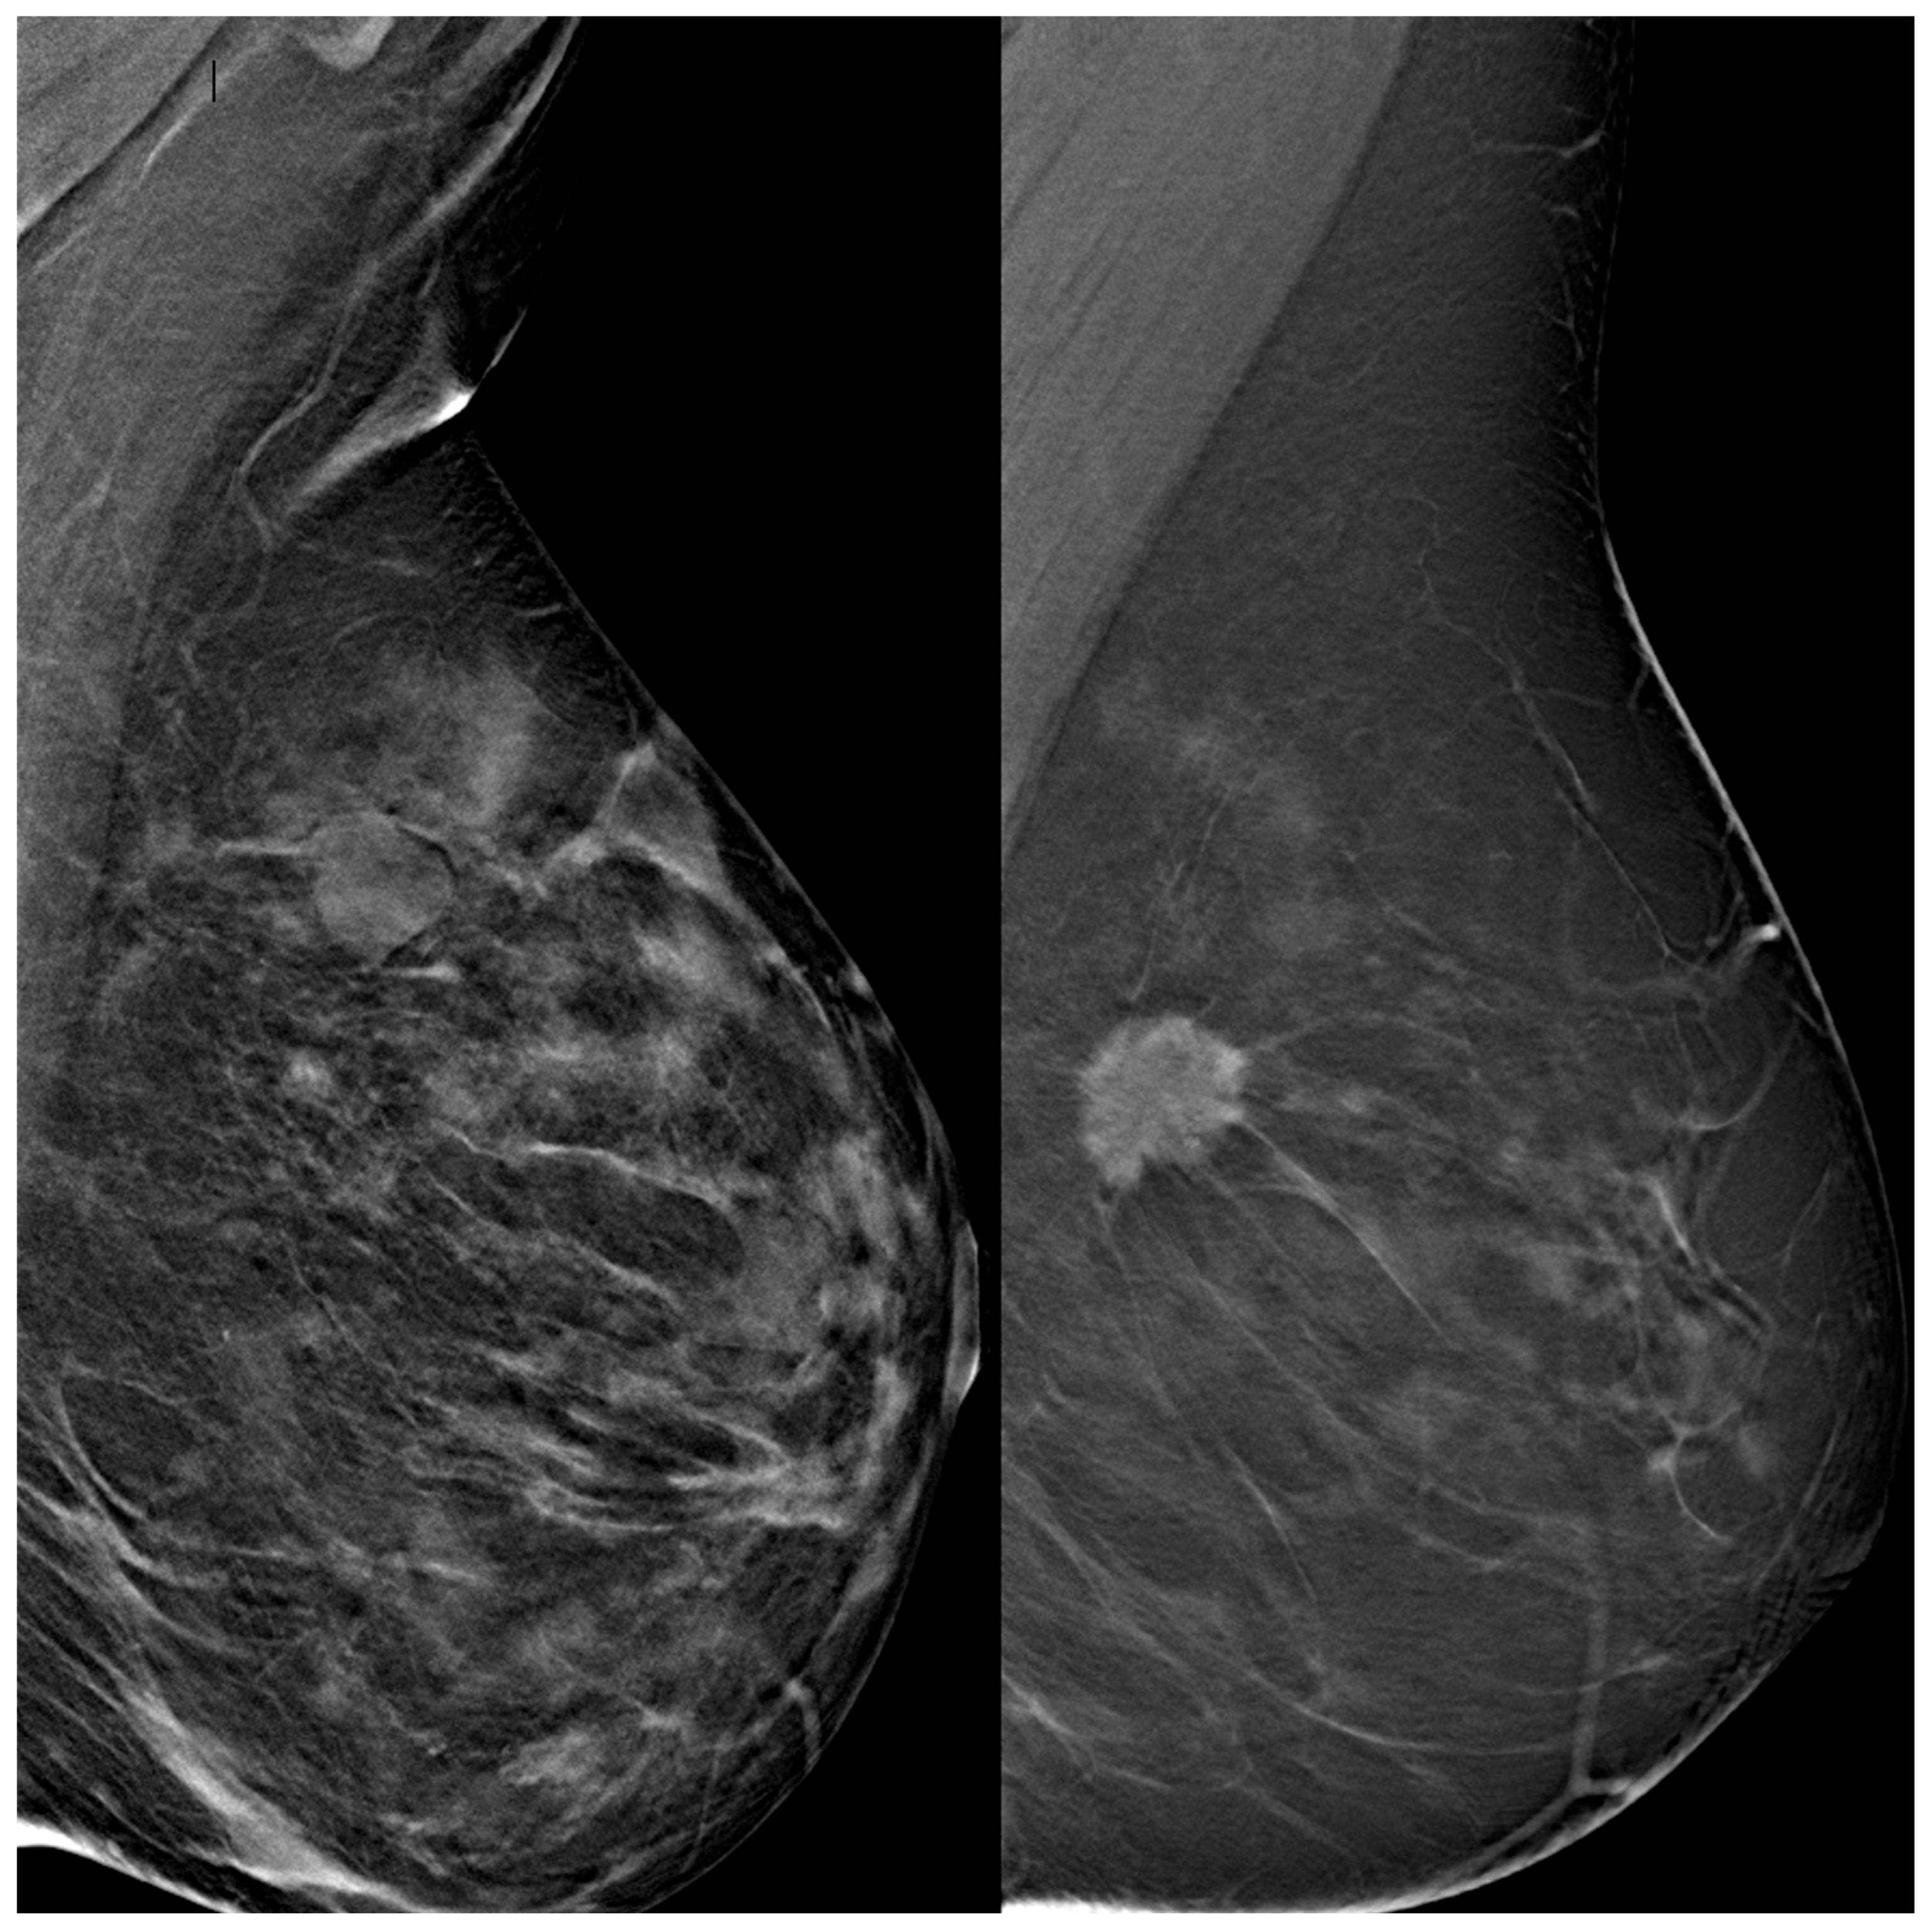

Figure 2. Representative digital breast tomosynthesis (DBT) cases used in the study. The left panel shows a negative case with no radiological evidence of malignancy, classified as BI-RADS 2 and confirmed negative at one-year follow-up. The right panel presents a positive case with a spiculated mass consistent with malignancy, classified as BI-RADS 5 and confirmed as invasive carcinoma on histopathological analysis. Both cases were included in the training dataset and segmented for deep learning model development.